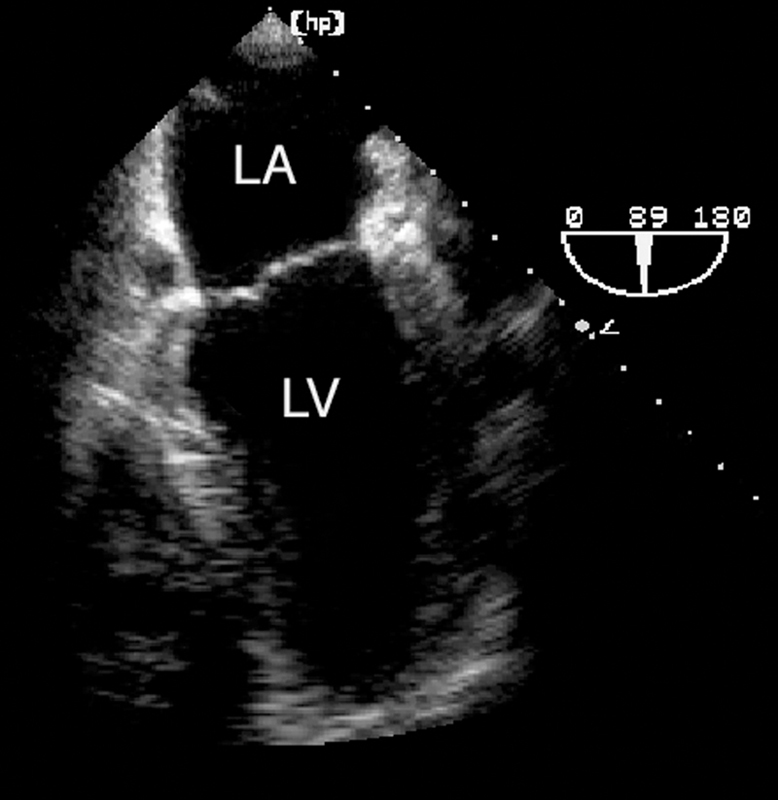

فحوصات تشخيصية لبعض امراض القلب والشرايين التاجية